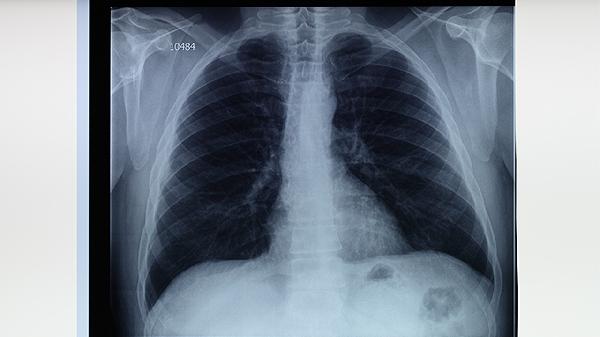

預防肺結核需建立健康生活方式,保證每日30分鐘有氧運動如快走、游泳。飲食注意增加瘦肉、深色蔬菜和菌菇類攝入,限制高糖高脂食物。高危職業(yè)人群應每年進行胸部X線檢查,出現(xiàn)可疑癥狀立即到結核病定點醫(yī)療機構排查。患者衣物寢具需煮沸消毒,痰液要用含氯消毒劑處理。全社會共同參與結核病防治,可有效阻斷傳播鏈。